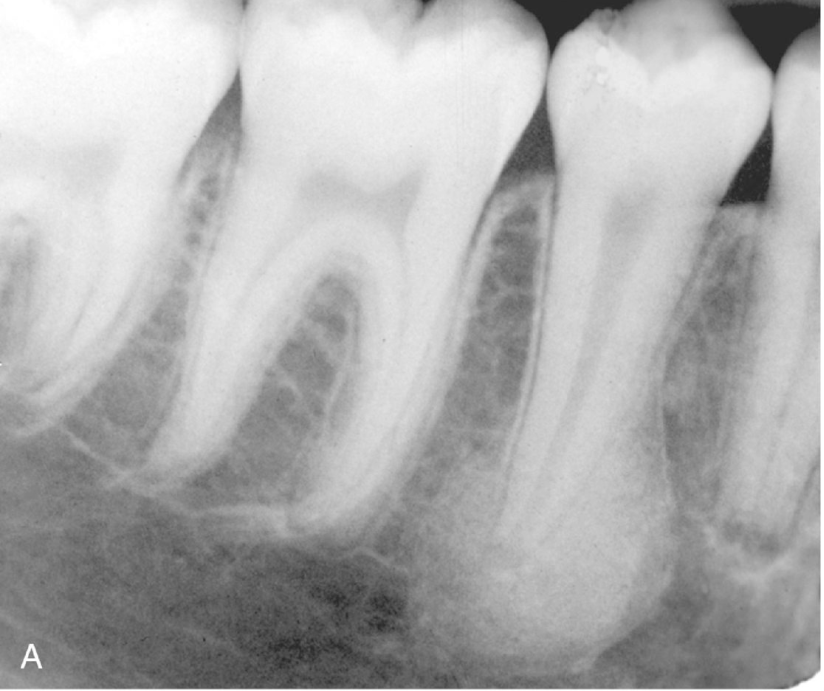

Focal osteoporotic marrow defect

Area of hematopoietic marrow – producing a radiography lucency (varies in size)

Marrow has pushed the bone away creating a defect

NOT PATHOLOGY - asymptomatic and incidental finding on radiograph

Radiolucency - ill defined borders with fine central trabeculations (multilocular)

Occurs in posterior mandible typically

NO jaw expansion

Biopsy is required for diagnosis – will just have bone marrow

No treatment necessary

No association with any hematologic disorder